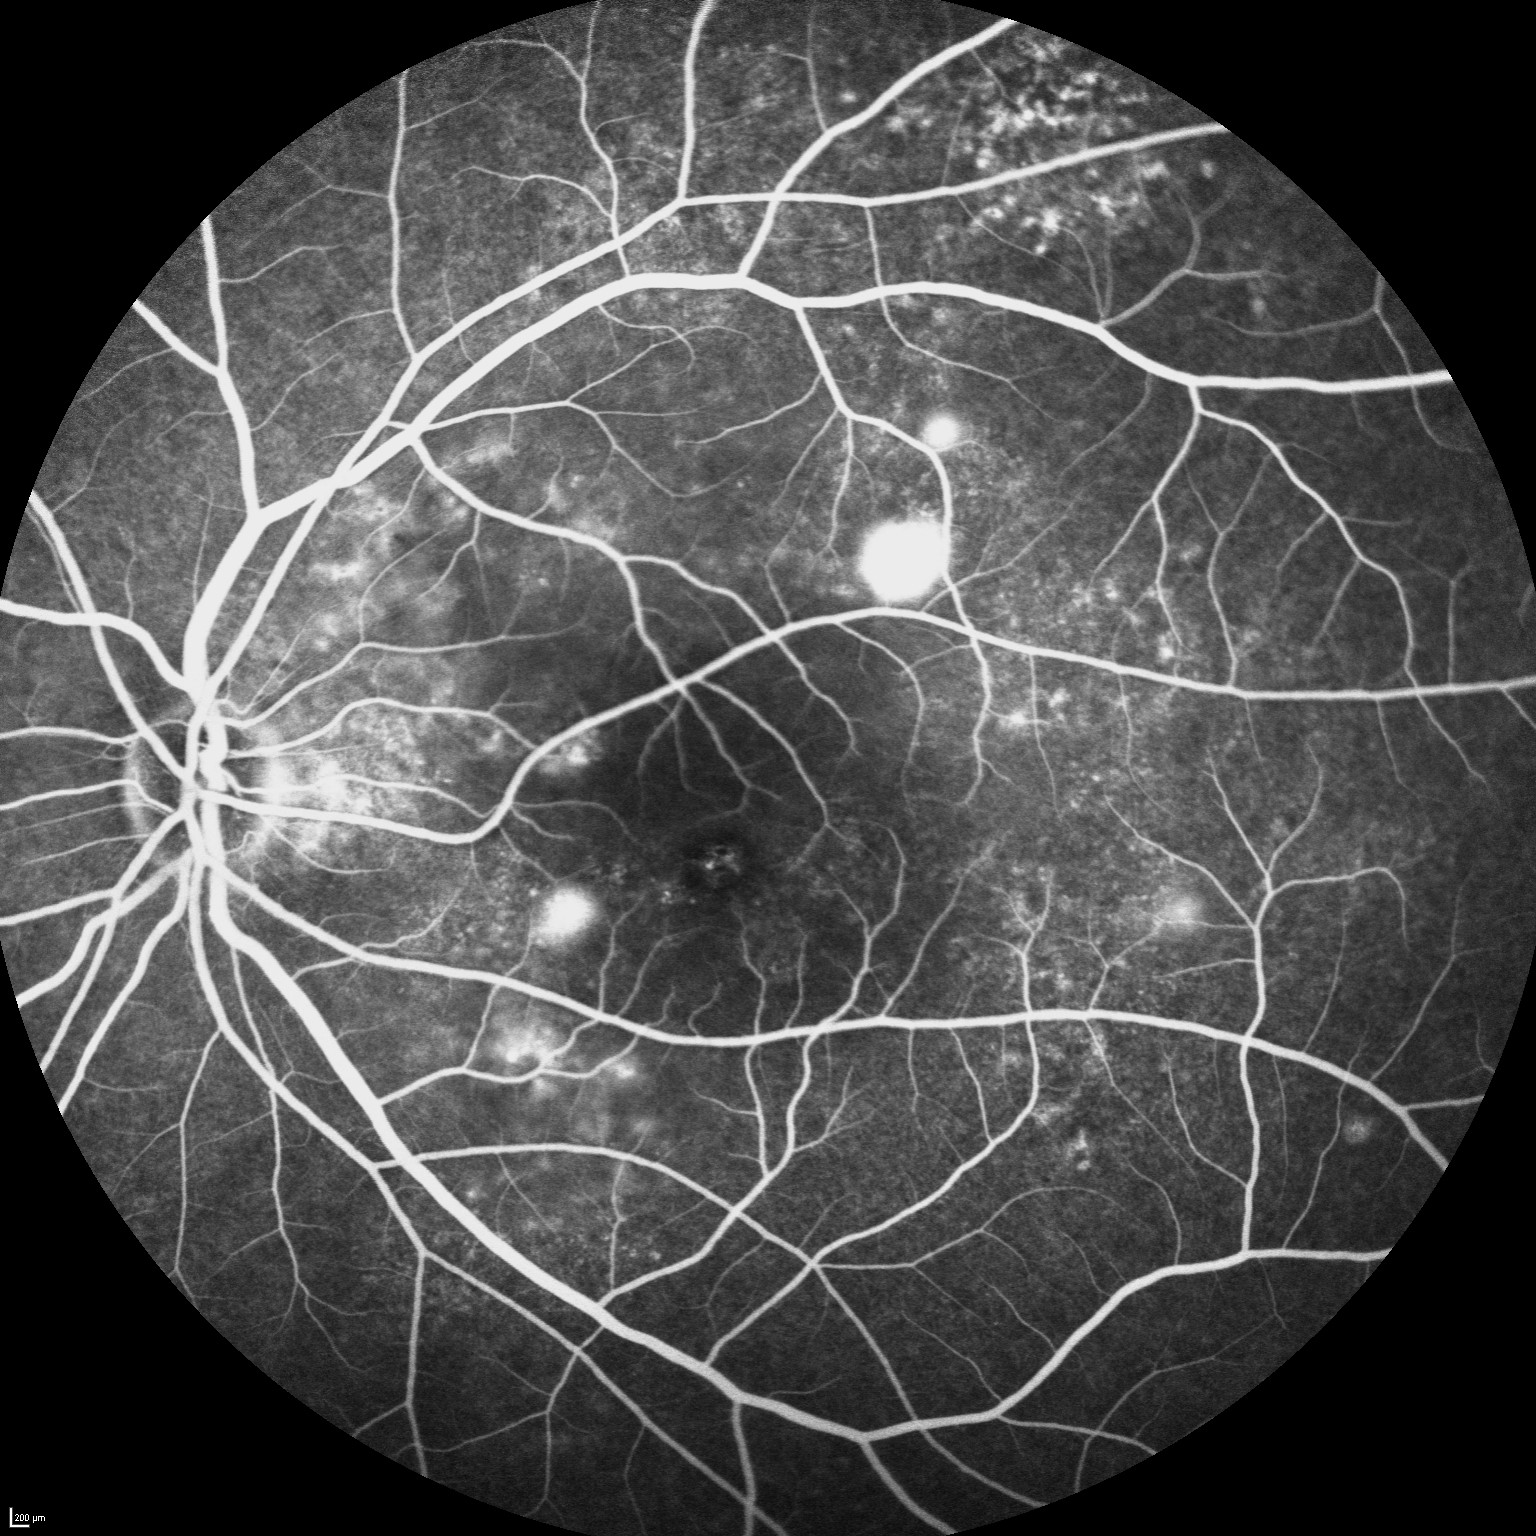

A comprehensive eye examination will need to be performed to confirm the diagnosis and determine the best treatment option. This may include OCT scan, retinal photography, fluorescein angiography, and indocyanine green angiography.